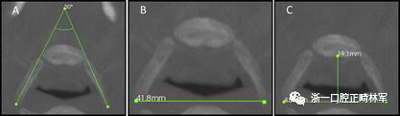

使用CS 3D成像軟件(版本3.4.3; Care-stream Health,Rochester,NY)進(jìn)行線性和角度測(cè)量。線性指標(biāo)包括鼻前后棘間距(ANS-PNS距離),咽腔最短距離(最短距離),咽腔C1的前后距離(APC1),咽腔C1的側(cè)壁間距離(LLC1),咽腔C2的前后距離(APC2),咽腔C2的側(cè)壁間距離(LLC2),咽腔C3的前后距離(APC3),咽腔C3的側(cè)壁間距離(LLC3),咽腔-會(huì)厭基底的前后距離(AP會(huì)厭),咽腔-會(huì)厭基底的側(cè)壁間距離(LL會(huì)厭),下頜骨兩側(cè)間的距離(L下頜骨),下頜骨的前后距離(AP下頜骨),舌骨兩側(cè)間的距離(L1舌骨)以及舌骨的前后距離(AP舌骨)。下頜骨前后角度的測(cè)量(下頜AP角),下頜橫角(TA下頜骨)和舌骨橫角(TA舌骨)。測(cè)量結(jié)果列于表I和圖1-4中。

圖3.A,舌骨橫角; B,LL舌骨; C,AP舌骨。

圖4. A,下頜橫角; B,LL下頜骨; C,AP下頜骨。

為了進(jìn)行線性測(cè)量,所有CBCT檢查都根據(jù)要測(cè)量的結(jié)構(gòu)進(jìn)行定向。對(duì)于咽腔,垂直參考線位于正中矢狀面內(nèi),水平線在前鼻棘和后鼻棘的軸向和矢狀重建之中。對(duì)于下頜骨,水平線在矢狀重建中切向定位在下頜骨的下緣,然后向上移動(dòng)至頦結(jié)節(jié)。對(duì)于舌骨,軟件定位線在矢狀重建中定位在該骨的長(zhǎng)軸上。